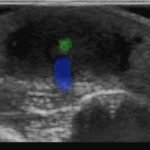

X-rays of the foot were obtained and no radiopaque foreign body was visualized. Due to high clinical suspicion for retained foreign body, a point-of-care ultrasound was performed by applying a high-frequency linear probe at the area of discomfort. In the long axis an ovoid focus of hypoechogenicity (orange outline) is visualized. Within this finding there is a linear focus (yellow line) of increased echogenicity measuring 1 mm in diameter and 1 cm in length. On short axis view, a rectangle focus (green dot) demonstrating shadowing (blue highlight) is seen.